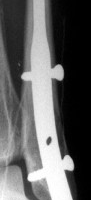

It is suitable for treatment of distal fibula fractures. After surgery the limb can be loaded immediately, it has a high patient-satisfaction index.

Main characteristics and advantages: